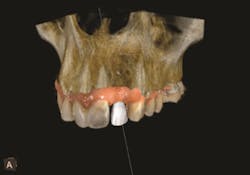

The interactive implant planning software provides multiple views, enabling the clinician to evaluate potential implant receptor sites with greater accuracy. Through the software, bone can be “removed” or displayed with transparency, which helps in determining the precise placement of implants, abutments and translucent virtual teeth in proximity to the natural tooth root structure. A virtual crown is used to guide the placement of the virtual implant for optimal aesthetics and function. This allows for well-informed conclusions to be drawn about crown-to-implant ratio; implant diameter and length; and the design of the restoration in terms of screw or cement retention.3 Figures 4-5.

Figure 4

Figure 5